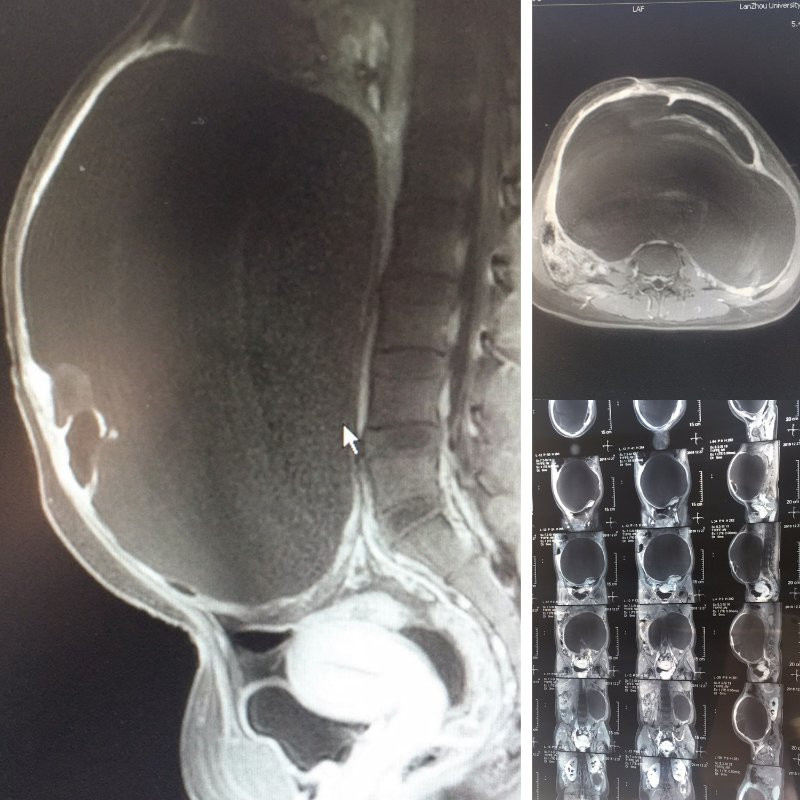

患者,女性,27岁,发现腹部包块两年,产后50余天突发腹痛,腹胀,高烧10余天由基层医院急诊转入我院,入院后完善相关检查发现患者重度贫血,低蛋白血症,腹部膨隆如足月妊娠大小,经核磁检查提示盆腹腔巨大囊性包块,初步诊断为巨大卵巢肿瘤蒂扭转并发感染。在积极纠正全身状况同时,我院妇科主任医师高峻、李丽萍带领团队成员周密筹划手术方案,在获得家属及患者的同意下,最终采用最微创的经脐单孔腹腔镜的术。术中发现肿瘤与肝区、脾区、肠管广泛紧密粘连,手术难度递增,医务人员沉着冷静、默契配合,经切口腹腔外穿刺放液,避免了囊内液流入污染腹腔,成功取出标本,术后患者疼痛轻、恢复快、创口小。